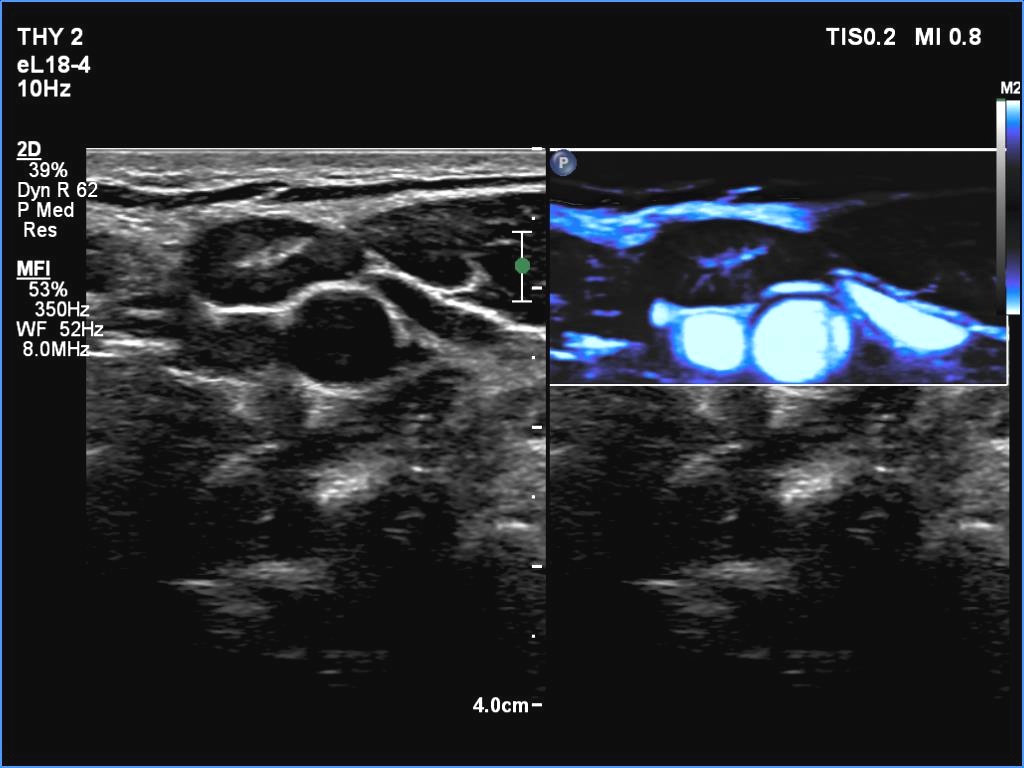

Introduction - case 462 (ultrasonographic picture 16)

Left submandibular area, longitudinal scan, microflow imaging. With this technique, vessels can be identified in the hilum; this is a crucial finding.